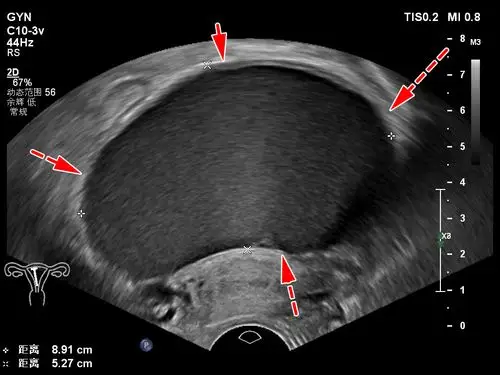

附院兖州院区超声医学科完成首例彩超引导微创硬化治疗卵巢巧克力囊肿